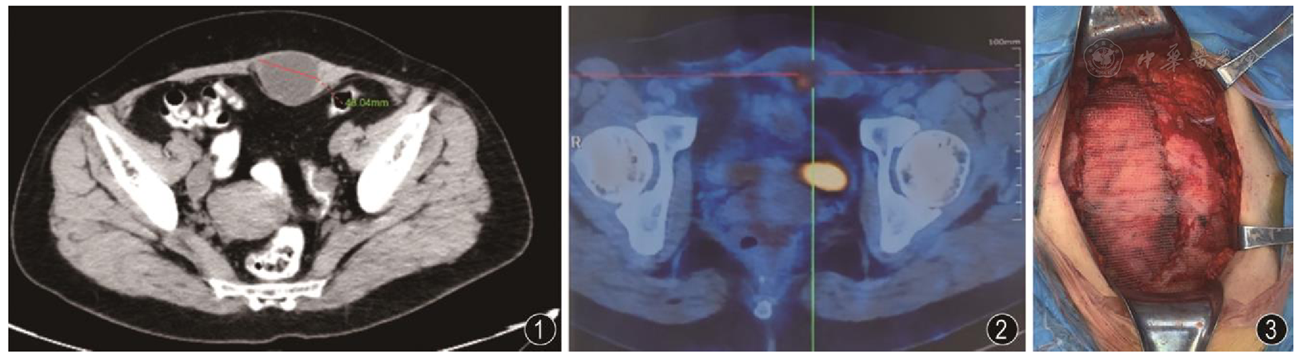

共检索出410篇文献,最终25篇(其中英文20篇,中文5篇)文献符合纳入标准,纳入31例剖宫产后AWE发生CCC患者。其中12例行单纯肿瘤切除,17例同时行肿瘤切除和附加手术,2例未行手术治疗。接受化疗的患者为21例,放疗者6例,同时接受放化疗者5例。2例接受了术前新辅助化疗。12例患者出现肿瘤的扩散或转移。23例有随访信息,随访期间死于疾病者4例,带病存活者8例,无疾病迹象者11例。本文报道1例AWE后发生CCC的患者,行病灶及部分腹壁切除后使用补片进行腹壁重建治疗,术后恢复良好。

AWE后发生CCC恶变的情况近几年有增加的趋势。目前对此类恶变过程缺乏有效的预防与观察手段,对AWE者应早期行病变切除手术。对发生恶变者,应行包括病灶在内的腹壁整块切除手术,形成的缺损可行包括应用补片的腹壁重建手术治疗。

图3 术中应用补片行腹壁重建